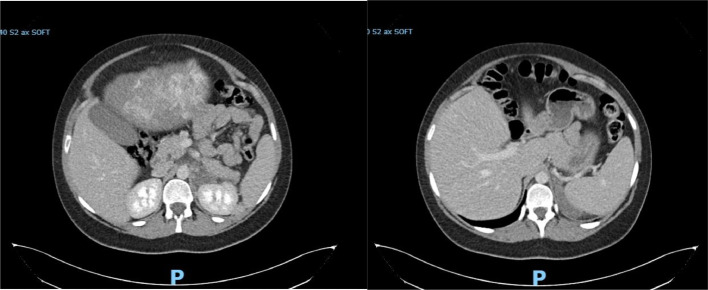

Adrenal haemorrhage in pregnancy is rare but can lead to significant maternal and fetal morbidity if unrecognised. We present the case of a 25-year-old woman in her second pregnancy, who was admitted at 34 + 4 weeks of gestation with severe abdominal pain. Despite initial unremarkable assessments, further imaging revealed a left adrenal haemorrhage, with evidence of prior right adrenal infarction, resulting in primary adrenal insufficiency. Haematological investigations later confirmed heterozygous factor V Leiden as a likely contributing factor. This report underscores the diagnostic challenges of adrenal pathology in pregnancy, where symptoms may overlap with more common conditions. Immediate management with hydrocortisone therapy, supported by a multidisciplinary team (MDT), was employed, with a successful outcome for both mother and child following delivery by caesarean section.

Abstract Image